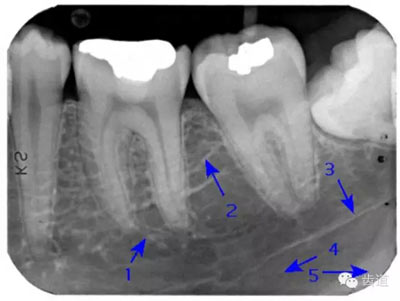

是機體中鈣化最高和最堅硬的組織,X線片上的影像密度也最高,似帽狀被覆在牙冠部牙本質(zhì)的表面。后牙頜面、前牙切緣最厚,由頜面和切緣向側(cè)方至牙頸部逐漸變薄,終止于牙頸部。

牙頸部Burnout征象:有時因投照技術(shù)問題而造成牙頸部近中或遠(yuǎn)中呈低密度影像,位于牙釉質(zhì)和牙槽嵴頂之間。

圍繞牙髓構(gòu)成牙的主體,牙本質(zhì)中礦物質(zhì)的含量比釉質(zhì)少,X線影像的密度較牙釉質(zhì)稍低。

被覆在牙根表面,為一層很薄的組織,密度與牙本質(zhì)相當(dāng) 。

髓腔可分為冠部的髓室和根部的根管。牙髓內(nèi)含牙髓軟組織,X線片上顯示為密度低的影像。年輕人的牙、牙根未完全形成時,根尖孔粗大,牙髓腔大。隨著年齡的增長,牙本質(zhì)逐漸增多,髓腔愈狹窄,根尖逐漸變細(xì)。

是上下頜骨包圍牙根的突起部分,又稱牙槽突或牙槽嵴。X線片上牙槽骨所顯示的密度較牙低。上牙槽骨的密質(zhì)骨薄,松質(zhì)骨多,即骨小梁數(shù)目多,相交處呈密度高的點狀影像,骨髓腔則呈點狀密度低的影像,固上牙牙槽骨的骨小梁結(jié)構(gòu)X線片上呈顆粒狀影像;

牙槽骨:下牙槽骨密質(zhì)骨厚而松質(zhì)骨少,骨小梁多呈水平方向排列,骨髓腔呈三角形和大小不等的圓形密度低的影像,所以下牙槽骨的骨小梁結(jié)構(gòu)呈網(wǎng)狀結(jié)構(gòu)

即固有牙槽骨,是牙槽骨的內(nèi)壁,圍繞牙根,骨質(zhì)致密而薄,X線片上顯示為包繞牙根的連續(xù)不斷的密度高的線條狀影像。

是介于牙槽窩和牙骨質(zhì)之間的結(jié)締組織。牙周膜的厚度一般在0.15~0.38mm之間。X線上顯示為包繞牙根連續(xù)不斷的密度低的線條狀影像,其寬度均勻一致